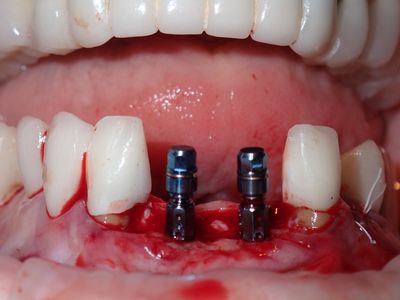

NSankhyan - immediate 13, impls 1121 and 25 with grafting

13 exo, loss of labial plate, implant placed buccal region grafted with sticky bone and collagen membrane soaked in prf fluid. 11/21 limited Labial-palatal width of bone, ridge split to 5mm, osteotomies prepared to about 2mm, remainder with densah drills, implants placed with ample bone, buccal grafted with same sticky bone. densah drills used for apical portion of 25 implant, soft bone, implant placed